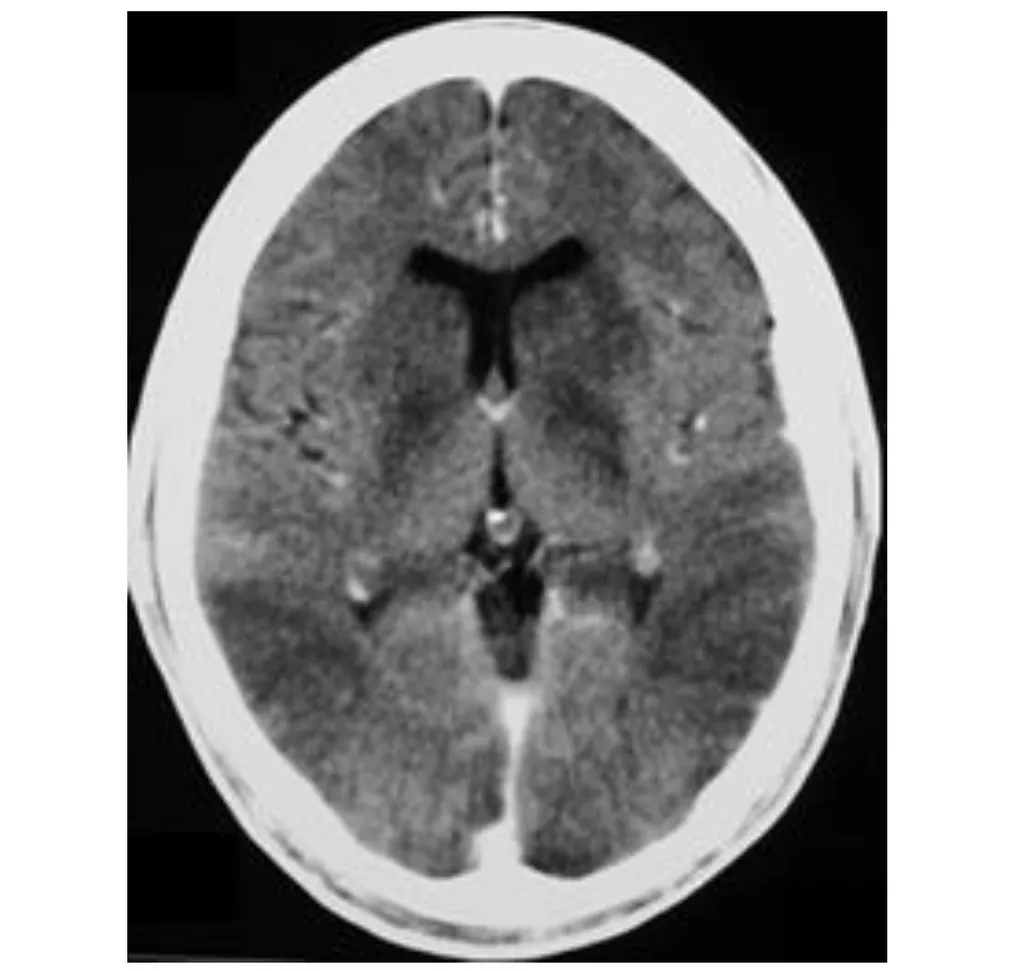

這道題的解題核心在於將臨床病史(急性心臟衰竭導致昏迷)與電腦斷層影像上呈現的瀰漫性腦水腫及灰白質分化不清的特徵結合起來。圖片中大腦整體密度降低,腦溝變淺,腦室受壓,這些都是缺氧缺血性腦病變的典型表現。